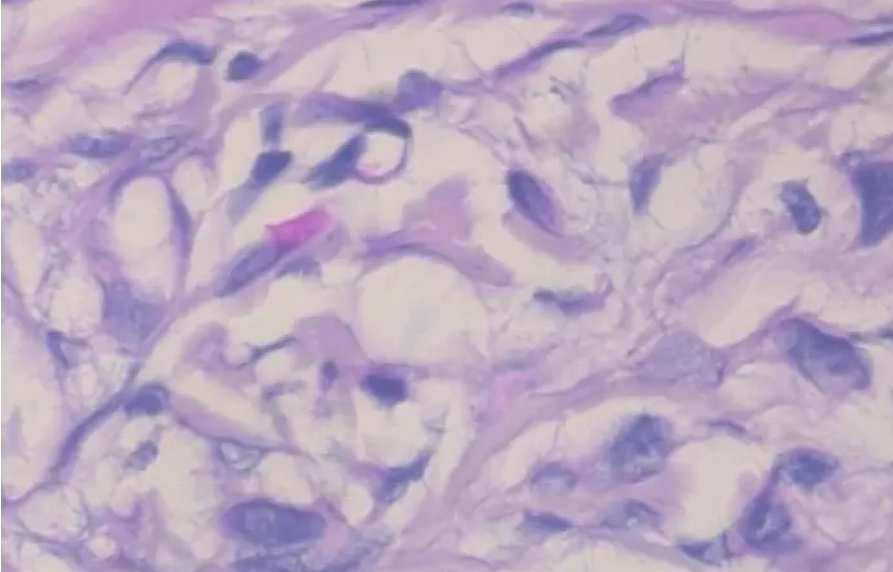

3.2 病变样本